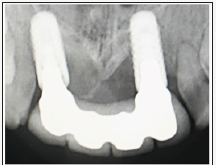

A 19-year-old Saudi male patient diagnosed with a Seckel syndrome reported to the clinic for replacement of upper anterior teeth #12, #11, #21, #22 (Figure 1). He was born to healthy, consanguineous (first cousins) parents. Patient’s mother reported that he was suffering psychologically because of his appearance and his inability to speak properly. Radiographic examination revealed that the remaining permanent teeth have erupted with minimal root development (Figure 2). Periodontal examination showed generalized moderate marginal gingivitis (Plaque score 35%, Bleeding score 15%). Oral hygiene regimen was given to the mother and full mouth gross scaling was performed. Informed consent was obtained for restoring missing teeth with dental implants. Medical clearance was achieved and implants were placed under nitrous oxide sedation and local anesthesia. A variety of tracheal tubes were at hand as many of these young patients have smaller trachea than would be suspected by age and physical size. A full mucoperiosteal flap was raised (Figure 3) and two implants (3.3x8BL- SLActive (Straumann –ITI) were placed in the area of #12 and 22 (Figure 4). Implant sites were grafted buccaly with bone graft (Puros Allograft –Cortico cancellous, Tutogen, Zimmer Dental) and covered with resorbable membrane (Copios pericardium – RTI Biologics, Tutogen, Zimmer Dental). Flap was repositioned and sutured with 4-0 resorbable Vicryl suture (Figure 5). Peri-apical radiograph was taken to show the position of the 2 implants in the edentulous sites (Figure 6). Three months post implantation period, the site was examined for bone and soft tissue healing around the implants to ensure osseointegration. A four-unit implant supported screwretained porcelain fused to metal bridge was attached (Figure 7) and peri-apical radiograph was taken to ensure complete and accurate fitting of the bridge (Figure 8). Occlusion was checked and oral hygiene instructions were given to the mother. The case was followed up for three years (Figure 9). The osseointegration was excellent with no untoward findings. Also, upon follow up, it was noted that the patient was considerably happier and the mother reported that the procedure has changed her son’s life. To the best of the author knowledge, this is the first report of implant supported fixed partial denture in Seckel Syndrome patient [4,7-10].

Figure 6: Peri-apical radiograph showing the position of the 2 implants.

Figure 8: Insertion of a screw retained 4-units PFM bridge supported by the 2 implants at #12, 22